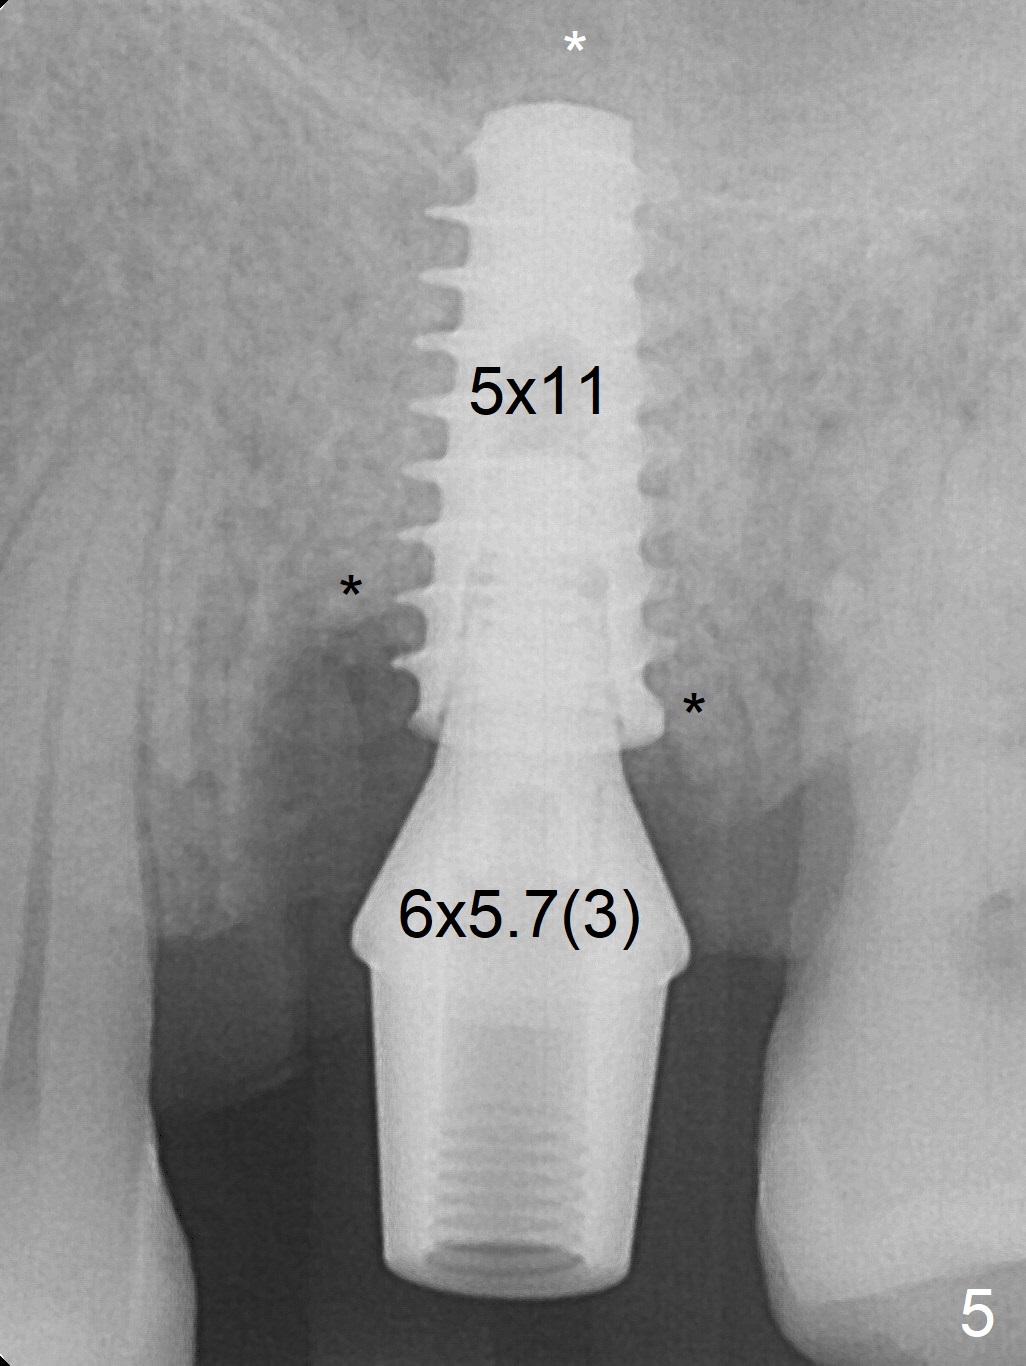

The ridge over the mobile tooth #14 is wide, suggesting bruxism pathogenesis (Fig.1). In spite of calculus over the roots of the extracted tooth (Fig.2), the septum remains. Osteotomy is initiated in the palatal slope of the septum (Fig.3,3' red dashed line). A 4.3 mm Magic Drill (MD) cannot bite into the bone probably because of the slope. Sequential osteotomy has to be done, starting with the smallest MD until 4.8 mm one. A 5x9 mm dummy implant is placed with 50 Ncm (Fig.4). To place 5x11 mm IBS implant (Fig.5), 5.3 mm MD has to be used; prior to implant placement, sinus lift is accomplished with mixture of autogenous bone and Vanilla graft (white *); more allograft (black *) is placed around the implant before insertion of a 6x5.7(3) mm abutment. More allograft is placed around the abutment (Fig.6 *) prior to an immediate provisional fabrication. The grafted bone appears to become the native bone, although at the low density, 6.5 months postop (Fig.7). The implant at #14 appears to have been placed in the middle of the alveolus buccopalatally (Fig.8).